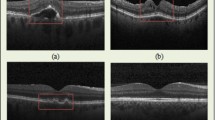

- Optical coherence tomography

(OCT). A non-invasive technique for fundus examination that produces cross-sectional images of the retina, retinal pigment epithelium and choroid.

Huang, D. et al. Optical coherence tomography. Science 254, 1178–1181 (1991). The invention of OCT.

Schmidt-Erfurth, U. et al. Three-dimensional ultrahigh-resolution optical coherence tomography of macular diseases. Invest. Ophthalmol. Vis. Sci. 46, 3393–3402 (2005).

The authors thank the following colleagues for permission to reproduce images: R. Cucu (Box 1c); G. Hageman (Fig. 5a–c); F. Holz (Box 1b); L. Johnson (Fig. 5d); R. Lewis (Fig. 2a,c); J. Sparrow (Fig. 3b); E. Stone (Fig. 2b; Box 1a); and H. Sun (Fig. 4a). The authors are supported by the National Institutes of Health (National Eye Institute) and the Howard Hughes Medical Institute.